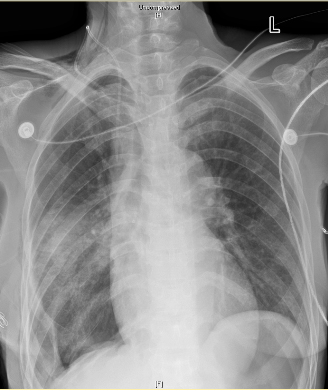

来自山东潍坊的代大姐今年51岁,20余天前因胸闷、憋喘,伴下肢水肿至当地医院行胸部CT检查,结果显示:考虑右侧胸腔巨大占位,伴右肺不张,符合恶性肿瘤表现。由于患者胸腔肿瘤巨大,当地医院认为手术切除十分困难,手术风险高,建议患者至上级医院就诊。患者辗转多家医院最后到省立医院胸外科刘相燕主任医师门诊就诊。刘相燕主任医师仔细阅读患者CT胶片及其他病历资料,评估患者病情后随即安排患者住院。

患者入院后复查胸部强化CT,结果显示右侧胸腔见巨大混杂密度团块,增强扫描动脉期病灶内见多发迂曲血管走行;纵隔明显左偏。患者胸腔瘤体巨大,国内外均较为罕见。不仅如此,由于长时间的肿瘤消耗,患者处于严重营养不良状态,白蛋白24.5g/L,血红蛋白89g/L。而且,患者右侧肺组织长期不张,肺功能FEV1仅有0.86L,MVV仅有23.78L/min,提示极重度混合性通气功能障碍。